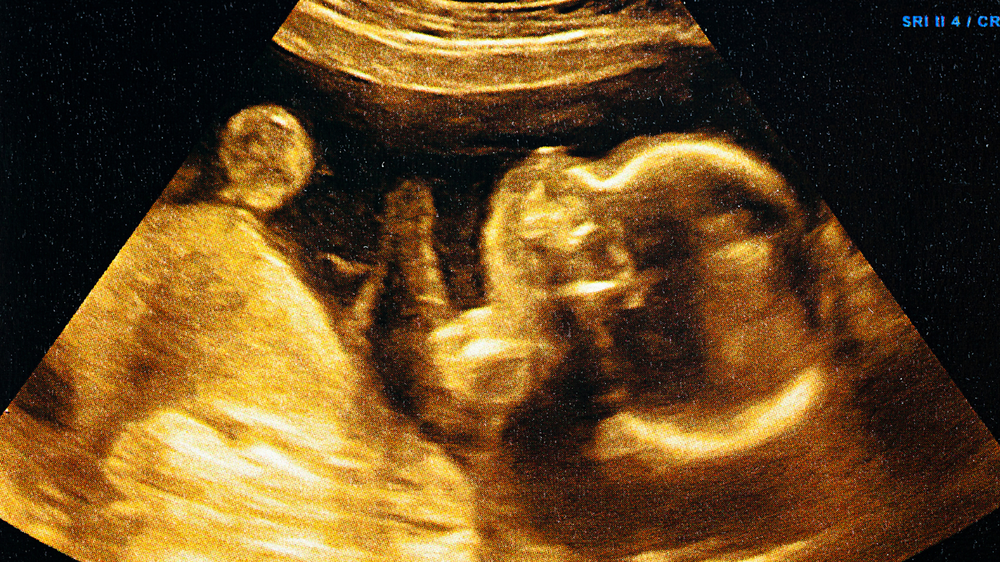

Your body produces several hormones during pregnancy to support your baby's growth. Oestrogen and progesterone are the two important hormones that work together to ensure the healthy development of your baby and prepare your body for childbirth. Knowing your body well helps you spot weird changes and get help if something doesn’t feel right.

Pregnancy is a remarkable miracle, with your body doing amazing things to grow your baby. Behind these changes, a couple of hormones are at work, with progesterone and oestrogen being the shining stars. You probably already know these are pregnancy hormones. What's more exciting is how they work together to help your baby grow and keep you healthy.